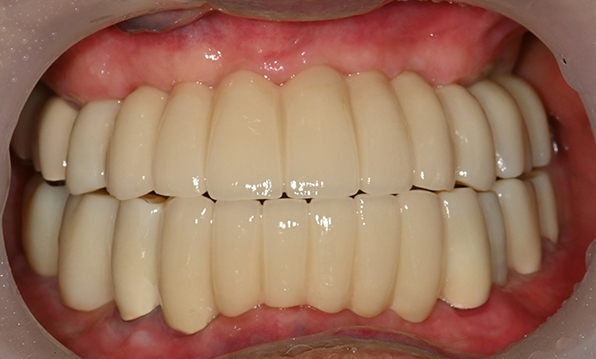

Before & After

Case 01

Before After